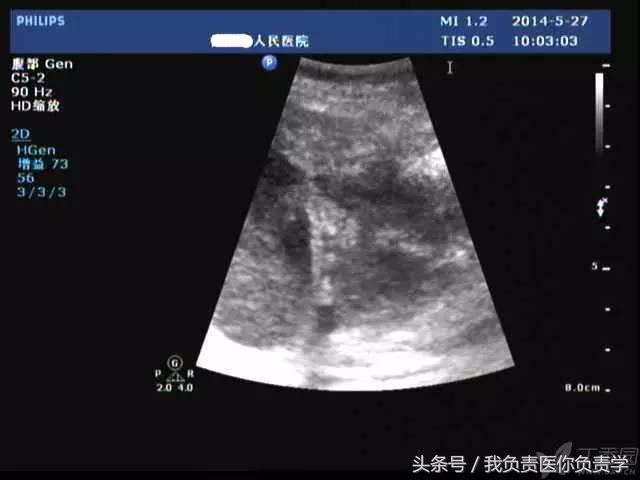

典型病例 1

患者男,64岁,因右上腹疼痛半月余就诊。查体发现右上腹部轻压痛,无发热。超声检查所见如下:

图3示胆囊与囊性回声区间隐约可见裂隙相通